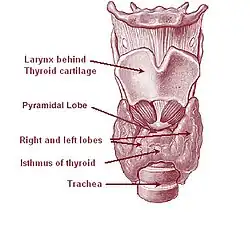

A glândula tireóide é um órgão em forma de borboleta composto por dois lobos, esquerdo e direito, conectados por uma estreita faixa de tecido, chamada de "istmo".[5] Ele pesa 25 gramas em adultos, com cada lóbulo tendo cerca de 5 cm de comprimento, 3 cm de largura e 2 cm de espessura, e o istmo cerca de 1,25 cm de altura e largura.[5] A glândula é geralmente maior nas mulheres do que nos homens e aumenta de tamanho durante a gravidez.[5][6]

A tireoide está perto da parte frontal do pescoço, apoiada e em torno da parte frontal da laringe e traquéia.[5] A cartilagem tireóide e a cartilagem cricóide ficam logo acima da glândula, abaixo do pomo de Adão. O istmo se estende do segundo ao terceiro anéis da traquéia, com a parte superior dos lobos estendendo-se até a cartilagem tireóide e a parte inferior em torno do quarto ao sexto anéis traqueais.[7] Os músculos infra-hióideos situam-se à frente da glândula e o músculo esternocleidomastóideo ao lado.[8] Atrás das asas externas da tireoide estão as duas artérias carótidas. A traquéia, a laringe, a faringe inferior e o esôfago ficam atrás da tireoide.[6] Nessa região, o nervo laríngeo recorrente[9] e a artéria tireoide inferior passam próximos ou no ligamento.[10] Normalmente, quatro glândulas paratireoides, duas de cada lado, situam-se em cada lado entre as duas camadas da cápsula da tireoide, na parte posterior dos lobos da tireoide.[5]

Às vezes, há um terceiro lóbulo presente, chamado lóbulo piramidal.[6] Quando presente, esse lobo freqüentemente estica o osso hióide a partir do istmo tireoidiano e pode ser de um a vários lobos divididos.[5] A presença desse lóbulo varia em estudos relatados de 18,3%[12] a 44,6%.[13] Mostrou-se que surge com mais frequência do lado esquerdo e ocasionalmente se separa.[12] O lobo piramidal também é conhecido como pirâmide de Lalouette.[14] O lobo piramidal é um remanescente do ducto tireoglosso, que geralmente se deteriora durante a descida da glândula tireoide.[6] De fato, pequenas glândulas tireoides acessórias podem ocorrer em qualquer lugar ao longo do ducto tireoglosso, desde o forame ceco da língua até a posição da tireoide no adulto.[5] Um pequeno chifre na parte posterior dos lobos da tireoide, geralmente próximo ao nervo laríngeo recorrente e à artéria tireoidiana inferior, é chamado de tubérculo de Zuckerkandl.[10]